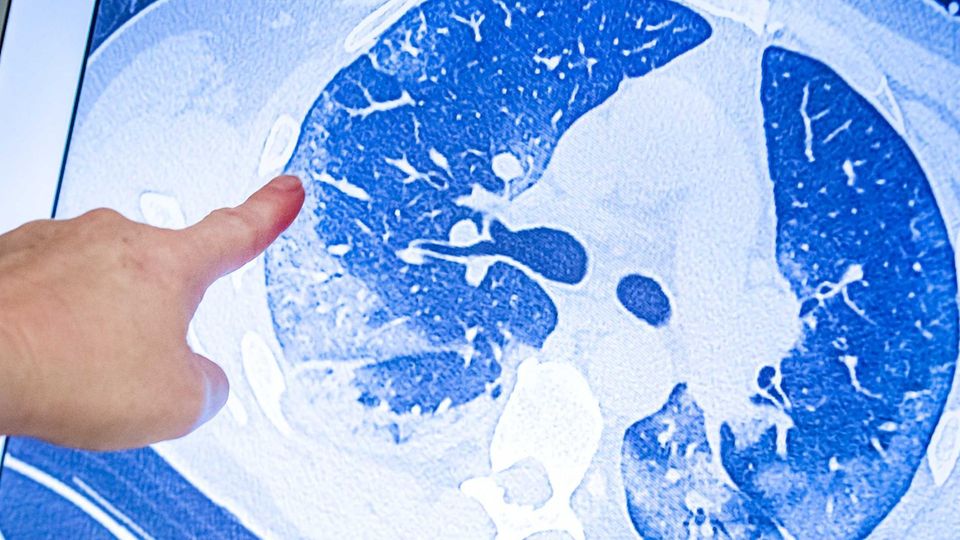

Ältere Menschen werden in Deutschland wie auch in Großbritannien und anderen Ländern mit Priorität geimpft, weil sie ein besonders großes Risiko für schwere Verläufe bei Covid-19 haben. Deshalb ist es wichtig, dass ein Impfstoff gerade auch Senioren gut schützt.